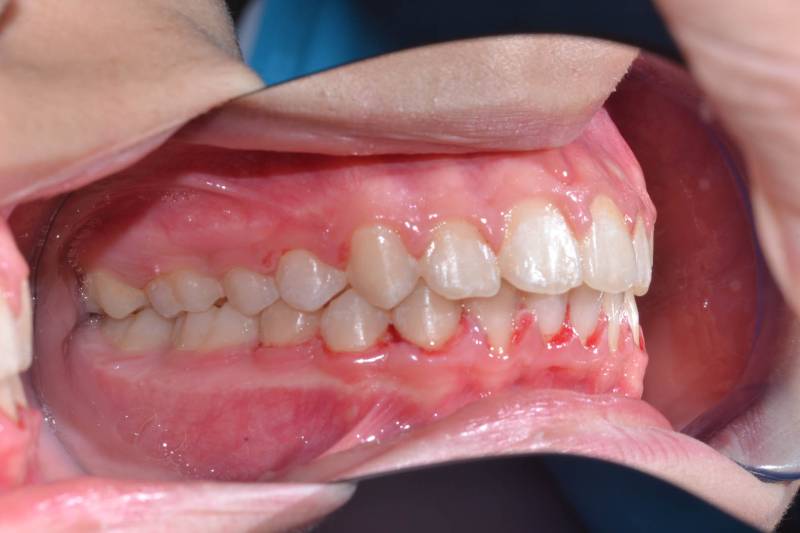

Paziente trattato con ortodonzia fissa bimascellare per 20 mesi.